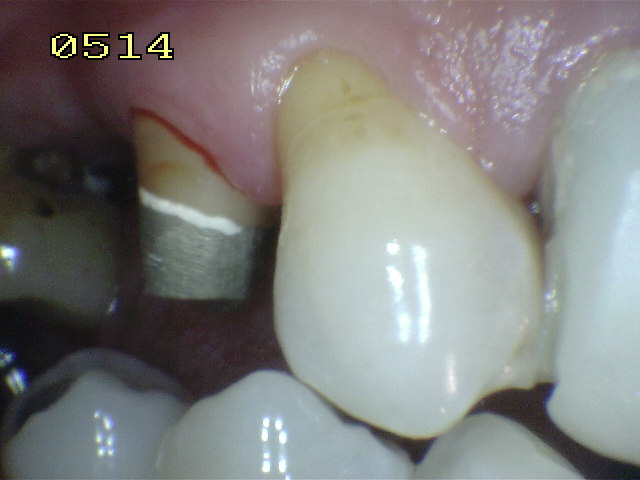

Una corona provisional debe tener los siguientes requisitos:

Debe imitar

la forma, el volumen y matiz de la pieza dental homóloga

contralateral.

La

adaptación marginal, (relación cuello dentario - encía marginal)

debe tener solución de continuidad para evitar la acumulación de

placa bacteriana y los contactos inter-proximales deben

ofrecer una resistencia moderada al pasaje del hilo dental. Este

paso debe ser tenido en cuenta para mantener la integridad de la

papila interdental. y la salud del periodonto.